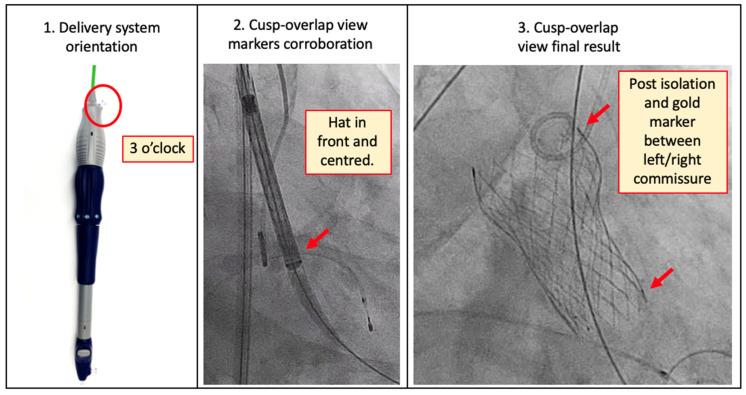

In current clinical practice, commissural alignment of the transcatheter heart valve (THV) during transcatheter aortic valve implantation (TAVI) is seldom achieved. Orientation of the THV within the aortic root and the subsequent influence upon leaflet haemodynamic function, coronary blood flow, and ease of access to the coronary ostia are gaining significant interest. Herein, we review the incidence and clinical implications of commissural misalignment in TAVI and offer thorough descriptions of how optimal alignment can be achieved with several different contemporary THV devices.

在当前的临床实践中,经导管主动脉瓣植入术(TAVI)期间经导管心脏瓣膜(THV)的瓣叶对合很少能够实现。THV在主动脉根部的定位以及对瓣叶血流动力学功能、冠状动脉血流和进入冠状动脉开口难易程度的后续影响正引起人们的极大兴趣。在此,我们回顾了TAVI中瓣叶对合不良的发生率及其临床意义,并详细描述了如何使用几种不同的当代THV装置实现最佳对合。